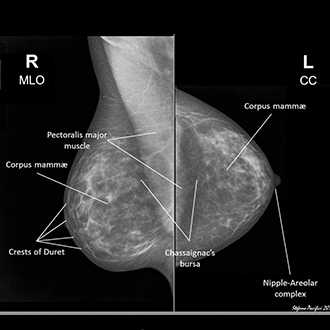

Equipment

Xtronics Xtromam 2000